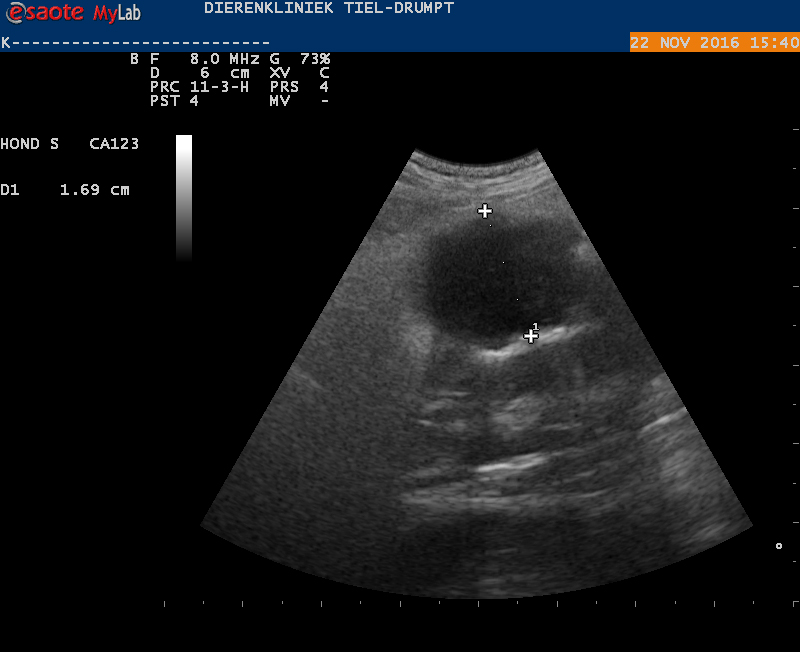

Om te weten wat er mis was, werd besloten een echo te maken.

Met de echo werden een aantal afwijkingen gezien. De belangrijkste waren een lokaal gebied van ontsteking en net boven een groot bloedvat was er een onregelmatig stuk darm te zien met een verdikte wand. Door alle veranderingen was niet goed te bepalen wat deze structuur exact was. Gezien het beeld en de leeftijd was de kans groot dat er sprake was van een tumor.